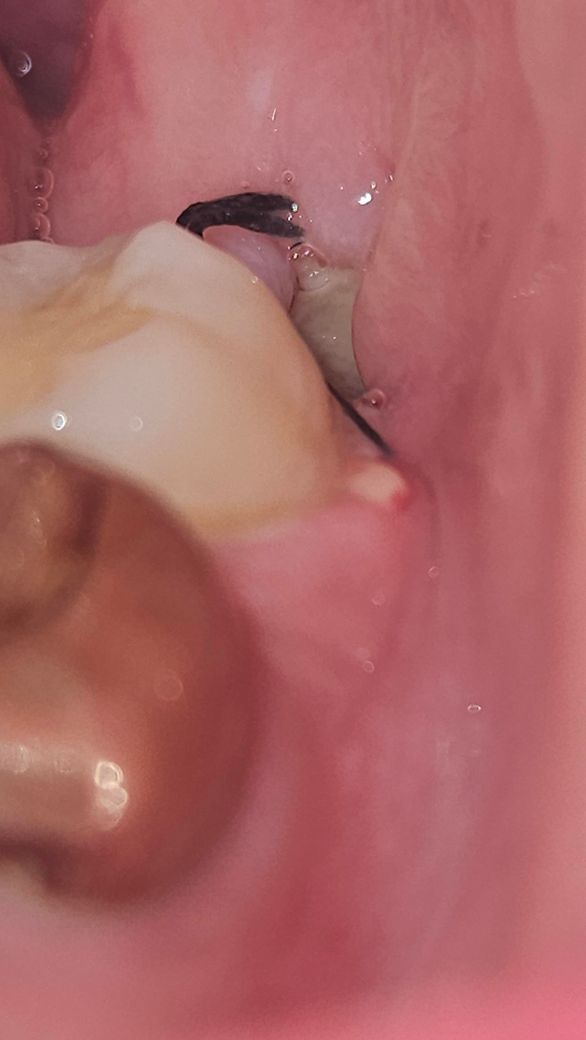

사진은 저게 최대고, 발치 구멍이 작은건지 안까지는 빛을 비춰도 잘 보이지 않네요. 드라이소켓 전조증상이 있을까요? 사진을 봤을 때 드라이소켓일 가능성이 높은가요? 앞에 구내염 때문에 이렇게까지 아플 수가 있나요? 만약 드라이소켓이라면 치료 방법은 무엇이고 치료의 고통 정도는 어느정도일까요?

• 2번 째 사진